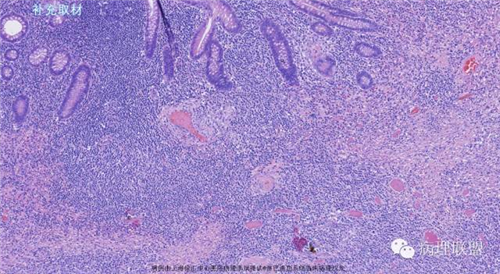

M,79岁,右半结肠粘膜下肿块。大小:6.5*6*6cm球形肿块,切面灰白质硬,界清。第一次取材。